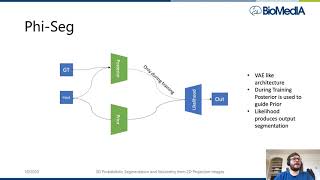

Tomographic Image Reconstruction: Introduction (Part 1) [L28] 3D Probabilistic Segmentation and Volumetry from 2D projection images

3D Probabilistic Segmentation and Volumetry from 2D projection images Beyond Local Processing: Adapting CNNs for CT Reconstruction

Tomographic Image Reconstruction: Introduction (Part 1) [L28] 3D Probabilistic Segmentation and Volumetry from 2D projection images

3D Probabilistic Segmentation and Volumetry from 2D projection images Beyond Local Processing: Adapting CNNs for CT Reconstruction